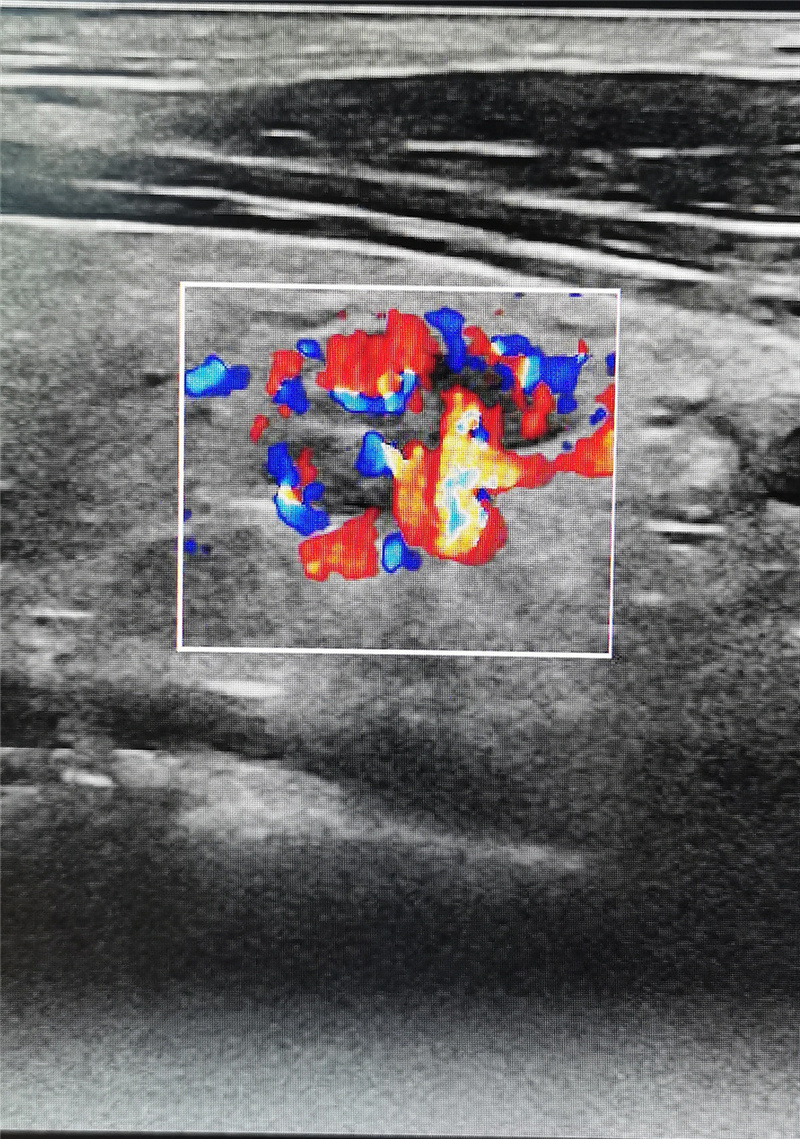

粤美特医疗健康体检中心从美国GE公司引进的目前彩超领域最先进的冰晶全“芯”超声影像设备,具备全球首创的血流显示技术,在MVI超微细血流成像、血管类造影成像和Radiantflow立体血流成像等方面引领世界,全方位、多维度显示血流灌注信息,帮助临床医生迅速成为具备火眼金睛、识别早癌妖魔的“肿瘤早筛孙悟空”。

在近期粤美特公司内部的一次关爱员工健康体检中,具备丰富临床经验、来自三甲医院超声科的陶枫主任运用美国GE冰晶超声影像设备,通过观察血流显示和结节形态,快速检查出一位员工长有1cm的甲状腺瘤,并给出了“高度疑似恶性中期甲状腺癌”的超声检查意见,后经北大医院穿刺活检证实了陶主任的判断是完全正确的,目前患者正在北大深圳医院住院手术治疗。

被查出的直径1cm恶性甲状腺瘤的立体血流成像图